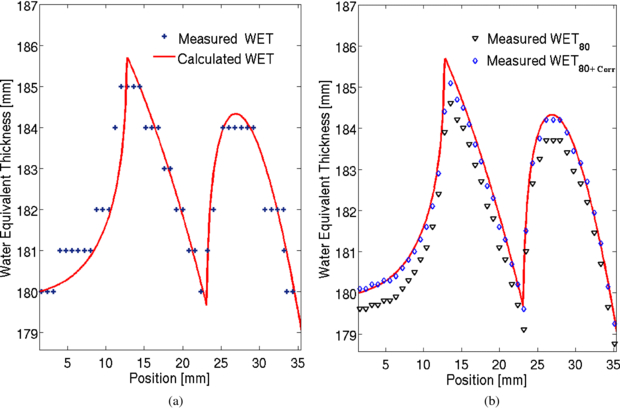

For validation of the energy scan method the WET distribution of a cylindrical PMMA phantom was measured. The signal as a function of the applied beam energy was obtained for each detector pixel. An example of such a curve is shown in figure 4. The obtained peak position corresponds to a certain initial beam energy Einit, max. It is translated into its corresponding water equivalent range (WET). The measured WET values are then given by the subtraction of the WETFlat-panel. They agree well with the expectation from the calculation (see figure 5(a)). The measured WET resolution is limited by the energy steps available from the accelerator. Due to the very different measured peak shapes it is not possible to fit for example a learning base-data set to the obtained signal curve to increase WET resolution. However, a possible way to increased WET resolution is by linear interpolation of the energy-signal curve and evaluation of S80 at which the signal amounts to 80% of the peak value at the steep descending flank of the peak, see figure 4. This idea is based on the fact that the descending flank is very steep and similar for all signal-energy curves. The WET80 value obtained at 80% of the signal increases WET resolution as seen in figure 5(b). However, the measured values are slightly lower than the calculated values. This underestimation can be quantified by investigation of the energy-signal correlation. When passing through matter, an ion experiences deflection caused by the Coulomb field of the nucleus. Neglecting multiple Coulomb scattering in homogeneous material, initial beam energy variation only shifts the Bragg peak in depth while preserving the peak shape. Therefore, the shift between the Smax and S80 value is nearly constant and can be used as a correction factor. Figure 5(b) shows the corrected WET80 values. They agree very well with the calculation. The standard deviations between the calculated and measured WET values are given in figure 6 indicated by the dashed lines. With the interpolation method the standard deviation decreases from 0.61 mm WET to 0.22 mm WET. However in the case of more complex imaging objects, the Bragg peak degrades due to multiple Coulomb scattering at material interfaces (Urie et al 1986). This Bragg peak degradation leads to an increased peak width; see figure 7. As a result the S80 is shifted here towards higher energy values. Correspondingly, the initial beam energy Einit, 80 is shifted to higher energies, which corresponds to smaller WET80 values. The effect of Bragg peak degradation is strongly correlated to the local inhomogeneity of the imaged object. For the WET measurement of our cylindrical PMMA phantom, minor Bragg peak degradation due to particle scattering and partial volume effect can explain the slight underestimation of measured WET value at the location of around 13 mm, indicated by the red arrow in figure 6.

Standard imageFigure 5. Comparison of the calculated and measured WET values. (a) Measured WET obtained at Smax. (b) Measured WET obtained at S80. A correction shift is applied to the measured WET values to agree well with the expected calculated WET distribution.

Download figure:

Standard imageFigure 6. Difference between calculated and measured WET values. Lines indicate one standard deviation. Larger deviation occurs at a position of around 13 mm indicated by the red arrow.

Download figure: